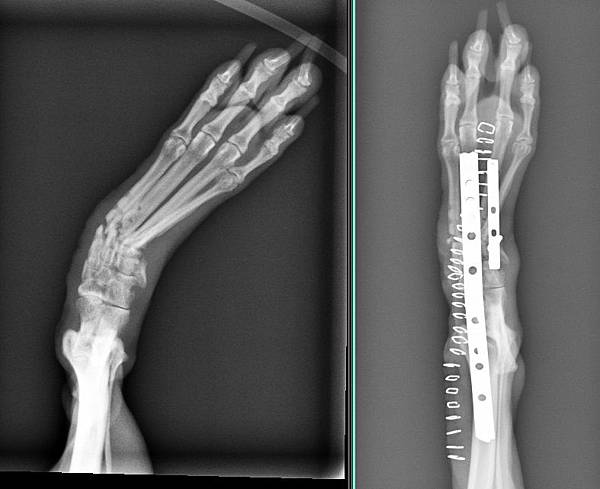

Apple來找小譚醫師的時候

說腳腳之前在南部有手術

但手術後鋼板裸露在外面而且依直流膿

所以來找小譚醫師想辦法

我們先將感染的鋼板移除

花了一個月養好傷口

這時候腳腳呈現一個非常不正常的姿勢無法行走

經過手術後

成功的讓腳腳恢復正常的姿勢

手術後兩周

我們醫療團隊成功的讓Apple恢復走跳的能力